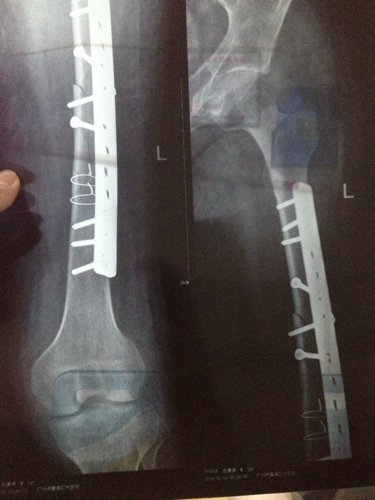

你好医生!左腿原来有小儿麻痹证,就在上个月11号不小心跌倒骨折13号做手术加钢板!现在在家休养。现在腰很痛?是怎么回事,有过性生活。现在简单吃两种药?请问医生像我这种情况会不会很难恢复原来那样?是不是还要吃些什么?还有要不要外敷些什么?还要腰很痛怎么办,谢谢!

病情分析: 图上所见,复位固定都还不错。 指导意见: 骨折的治疗重点是有效牢靠的固定。药物是次要的可以不服。也要注意尽量不要做对愈合不利的活动。除非是肌肉的锻炼等。